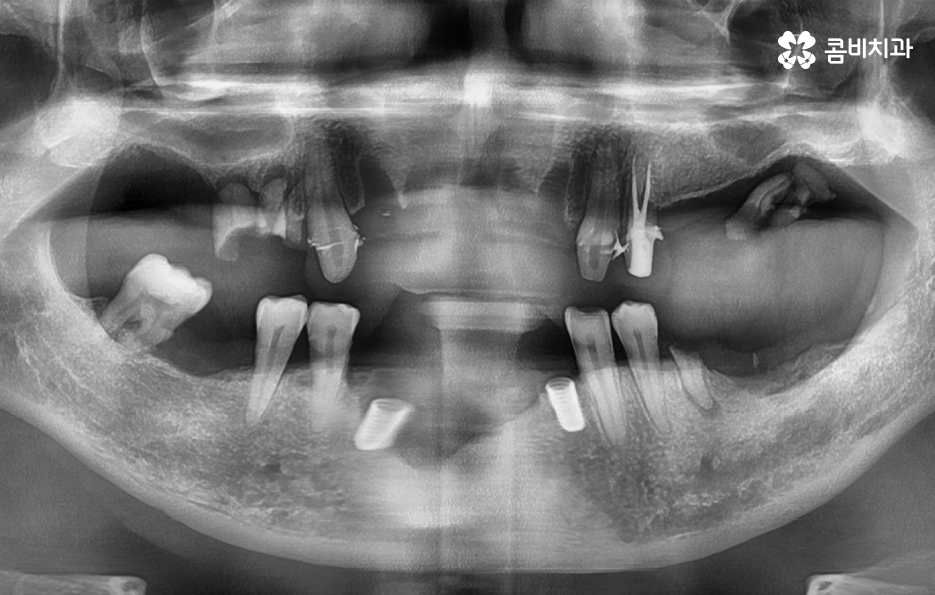

위 환자분의 엑스레이 사진을 보면 치아의 뿌리 부분에 가깝게 잇몸이 내려앉은 것을 볼 수 있는데 치아의 구조에서 뿌리쪽은 법랑질이 없기 때문에 잇몸이 내려앉고 잇몸 뼈가 치주염으로 녹게 되면 치아가 너무 아파서 식사를 하기에도 어렵고 물 한잔만 마셔도 이가 시릴 정도로 일상에 지장을 느끼실 수 있어요

결국 치아가 흔들릴 정도까지 잇몸 뼈가 녹고 치아의 뿌리도 함께 손상된다면 발치로 이어지겠지만 임플란트의 과정은 잇몸이 건강하신 환자분들과 잇몸이 약해지고 얇아지신 분들의 경우에는 치료적인 접근이 달라지기 마련인데 일반적인 임플란트의 경우 치아를 발치하고 임플란트를 올리기 까지 약 5~6개월 정도가 소요된다면 잇몸 뼈가 녹을 정도로 잇몸이 약해진 분들의 경우에는 뼈이식을 포함하여 경우에 따라서는 1년까지도 치료 기간이 걸릴 수 있기 때문에 임플란트 치료 역시도 어려운 과정을 겪게 될 수 있다는 점에서 치주염 발치의 경우 결코 가볍지 않은 시술 과정이 동반될 수 있어요

고령의 환자분들의 경우에는 잇몸 뼈의 상태 뿐 아니라 전신질환, 회복력을 함께 고려해야 하기 때문에 치료 계획에 있어서 보다 섬세하게 체크해야 하며 환자분의 잇몸 뼈 상태와 전신건강 그리고 경제적인 상황 등을 고려할 때 전체임플란트를 하게 되는 경우도 있지만 위 환자분의 사례처럼 임플란트를 최소한으로 식립하여 임플란트의 보철물을 연결하여 치아의 기능을 회복하는 경우도 있는데요